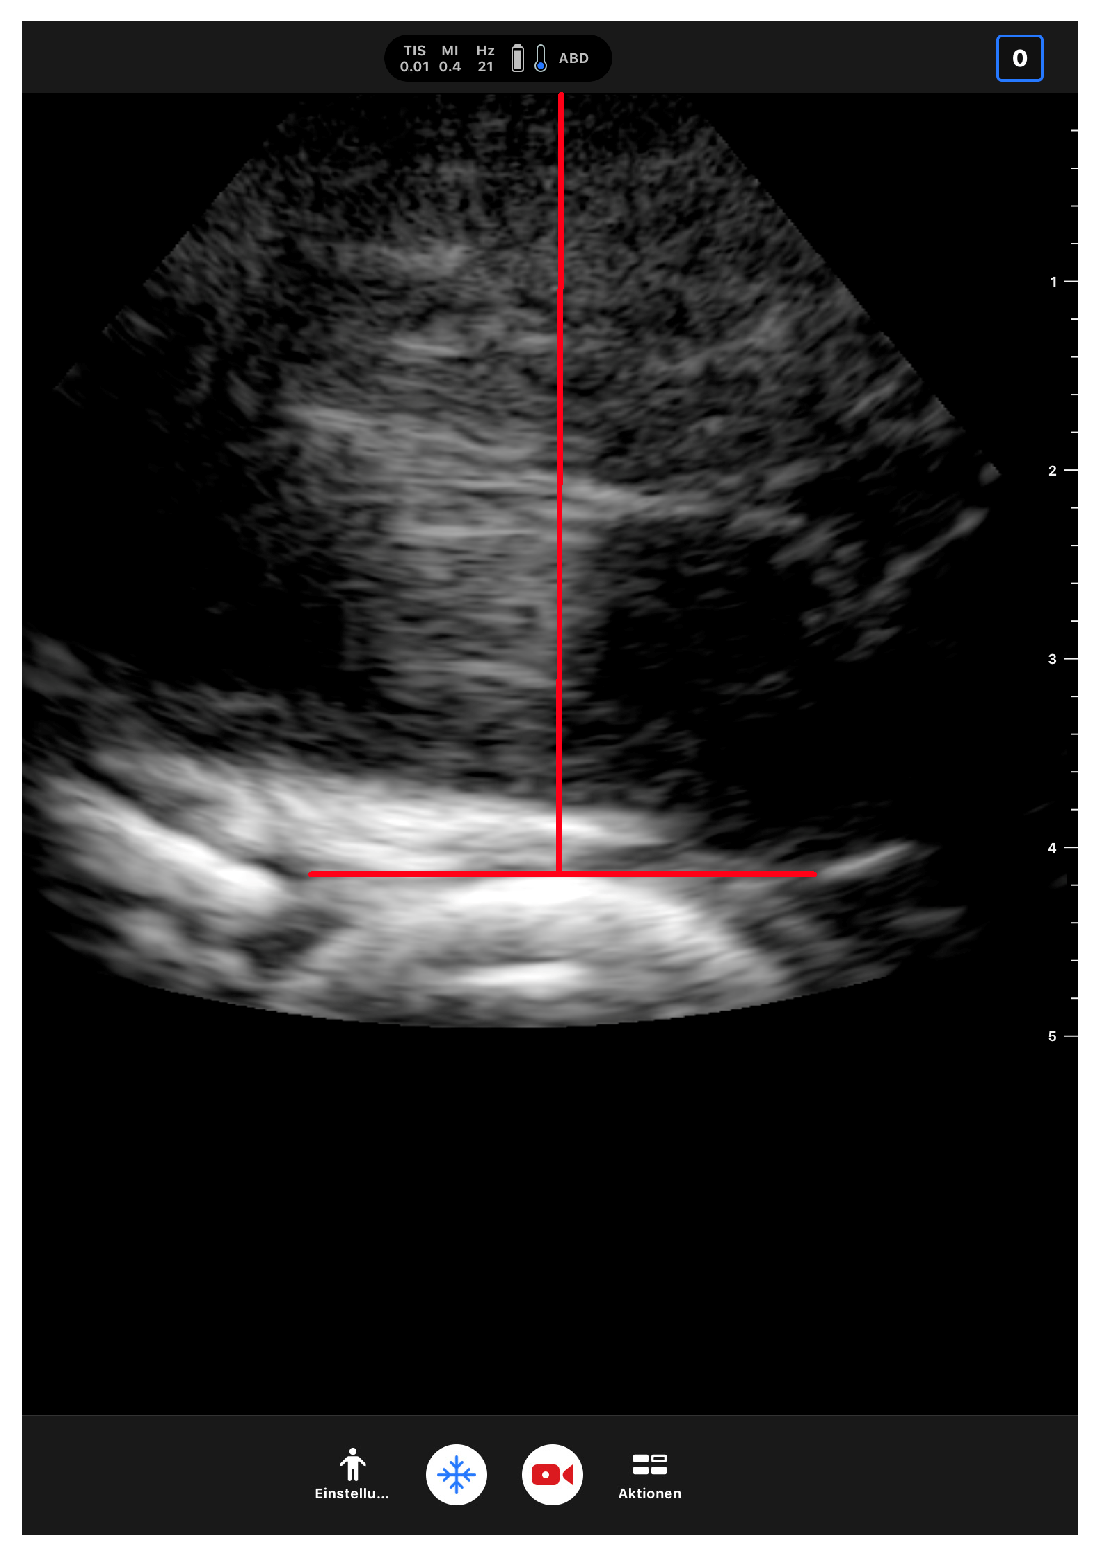

Preliminary Results of Measurements of Frontal Plane Knee Alignment Using a Standardized, Sonographic-Assisted Digital Photograph—A Reliable and Accurate Alternative to a Full-Leg Radiograph?

2. Materials and Methods